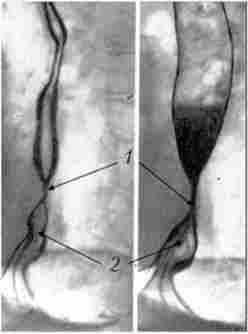

пептичні РСП можуть бути різної протяжності і майже завжди поєднуються з ГПОД. Коротка стриктура має вигляд симетричного звуження з рівними контурами довжиною 1-2 см (рис. 9.7).

Рентгенограма стравоходу при короткій пептичної стриктури на грунті ГПОД. Стравохід укорочений, частина кардіального відділу шлунку знаходиться в задньому середостінні

Мал. 9.7. Рентгенограма стравоходу при короткій пептичної стриктури на грунті ГПОД. Стравохід укорочений, частина кардіального відділу шлунку знаходиться в задньому середостінні:

Протяжна пептична стриктура циліндричної форми розташована в дистальній частині стравоходу. Довжина її може перевищувати

3-5 см. Стінки стриктури ригідні, складки слизової потовщені, звивисті. У ряді випадків в зоні звуження можна виявити виразкову нішу.